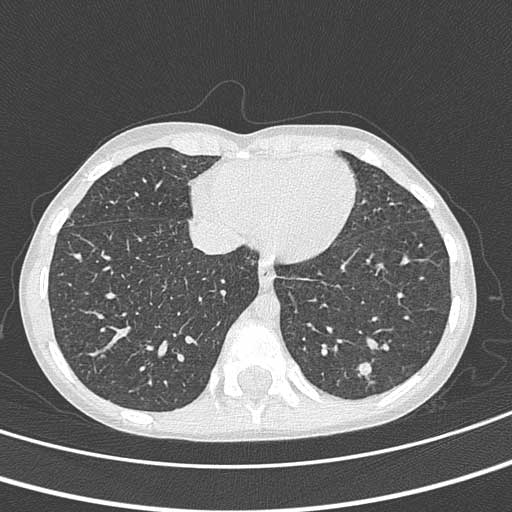

asintomatico. La TAC torace mostra multiple opacità

nodulari millimetriche a distribuzione random compatibile con

miliare tubercolare (mai avuta tosse). A 6 mesi dall’inizio

![]() Tac

Torace